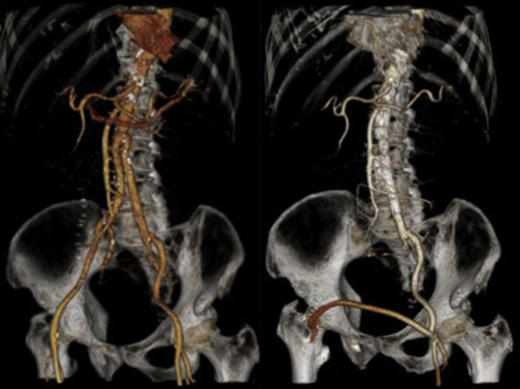

The ruptured group presented survival rates of 53.5%, 50.5%, 47.5%, 42.3%, 38.0%, 21.9%, and 12.5% at 1 year, 2 years, 3 years, 4 years, 5 years, 10 years, and 15 years, respectively; while the nonruptured group had survival rates of 91.5%, 88.0%, 83.7%, 78.3%, 73.0%, 43.0%, and 25.3% (log rank p < 0.001; Fig. 2). For those who died 30 days after their operation, only six patients died from aneurysm related causes, giving a late aneurysm-related mortality of 1.8% (Table 5). There were a total of three (0.9%) patients who underwent late re-interventions due to graft related events. The first patient underwent open repair in 1994 at the age of 66 years. The 4.4 cm infrarenal aortic aneurysm and 5.7 cm left iliac aneurysm were replaced with aorto-bi-iliac knitted Dacron graft. He presented with recurrent gastrointestinal bleeding of unknown origin 6 years later. Upper endoscopy and colonoscopy failed to localize the bleeding source. Laparotomy and enteroscopy showed suspicious bleeding from the proximal jejunum and possible graft-to-jejunum fistula. Bleeding was settled with aorto-uni-iliac endovascular stenting and cross femoral bypass. The patient is still alive to date (Fig. 3). The second patient underwent open repair with aorto-bi-femoral woven Dacron graft in 1993 at the age of 72 years. Seven years later, he was incidentally found to have a pulsatile mass at the epigastrium with a CT scan showing an infrarenal 8 cm proximal anastomosis pseudoaneurysm. Treatment was standard endovascular repair (Fig. 4). The last patient had open repair surgery with aorto-bi-iliac woven Dacron graft in 1993 at the age of 76 years. He complained of epigastric pain 20 years later with a CT scan showing a 9 cm proximal perivisceral pseudoaneurysm, which was settled with endovascular stenting with fenestration to all four visceral vessels (Fig. 5; Table 6). In addition, 17 (5.0%) patients developed thoracic or iliac aneurysms in later life. They were treated with open or endovascular repair (Table 7).

Late intervention, Patient 1.

Fig. 3.